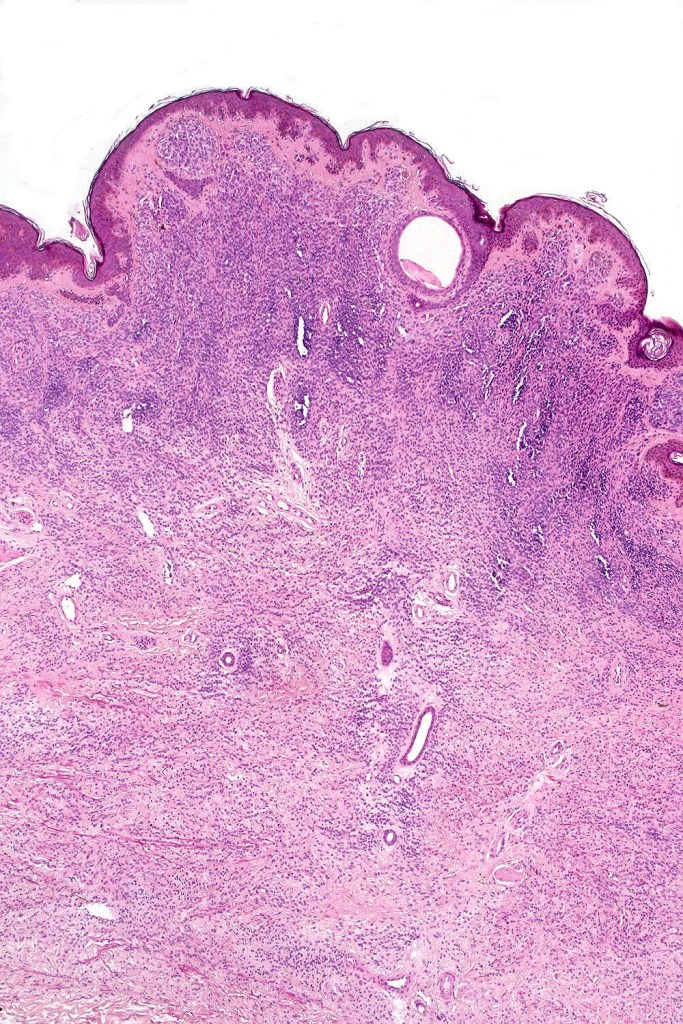

•Most often are distinctive at scanning/low power examination due to the depth of involvement

•Diffuse infiltrate of nevus cells often extending deeply into the dermis or beyond, single filing is often present at base & may involve the septa of the subcutaneous fat

•Involvement of appendages & arrector pili muscles

•Neurotization, neurofibroma-like lesions & neurocristic hamartoma

•Perineural sheath infiltration

•Blood vessel and lymphatic wall infiltration